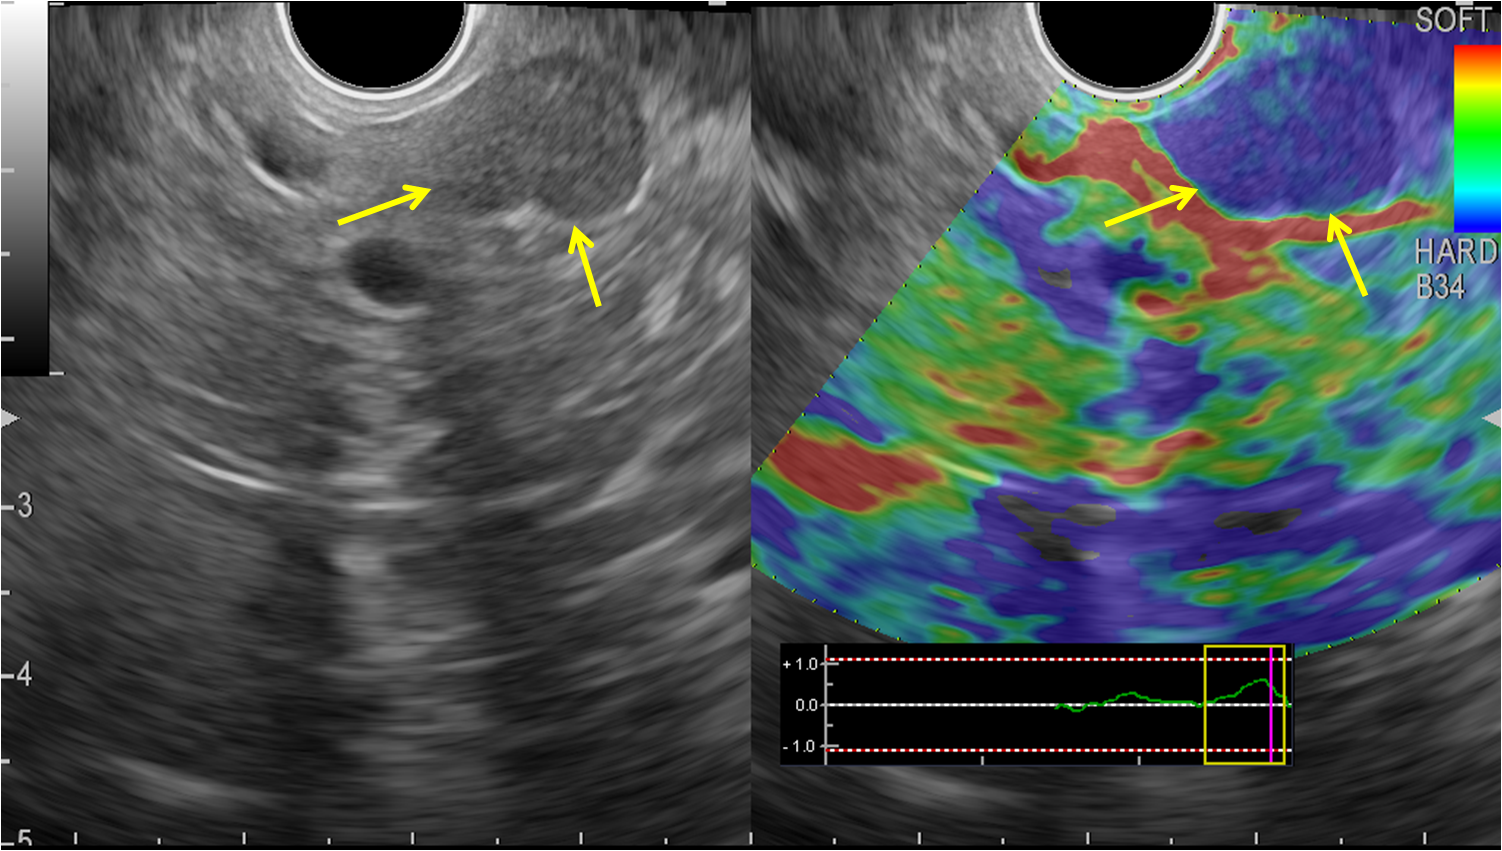

1. ЭУС - эластография новообразования поджелудочной железы: гетерогенный рисунок с преобладанием синего цвета | |